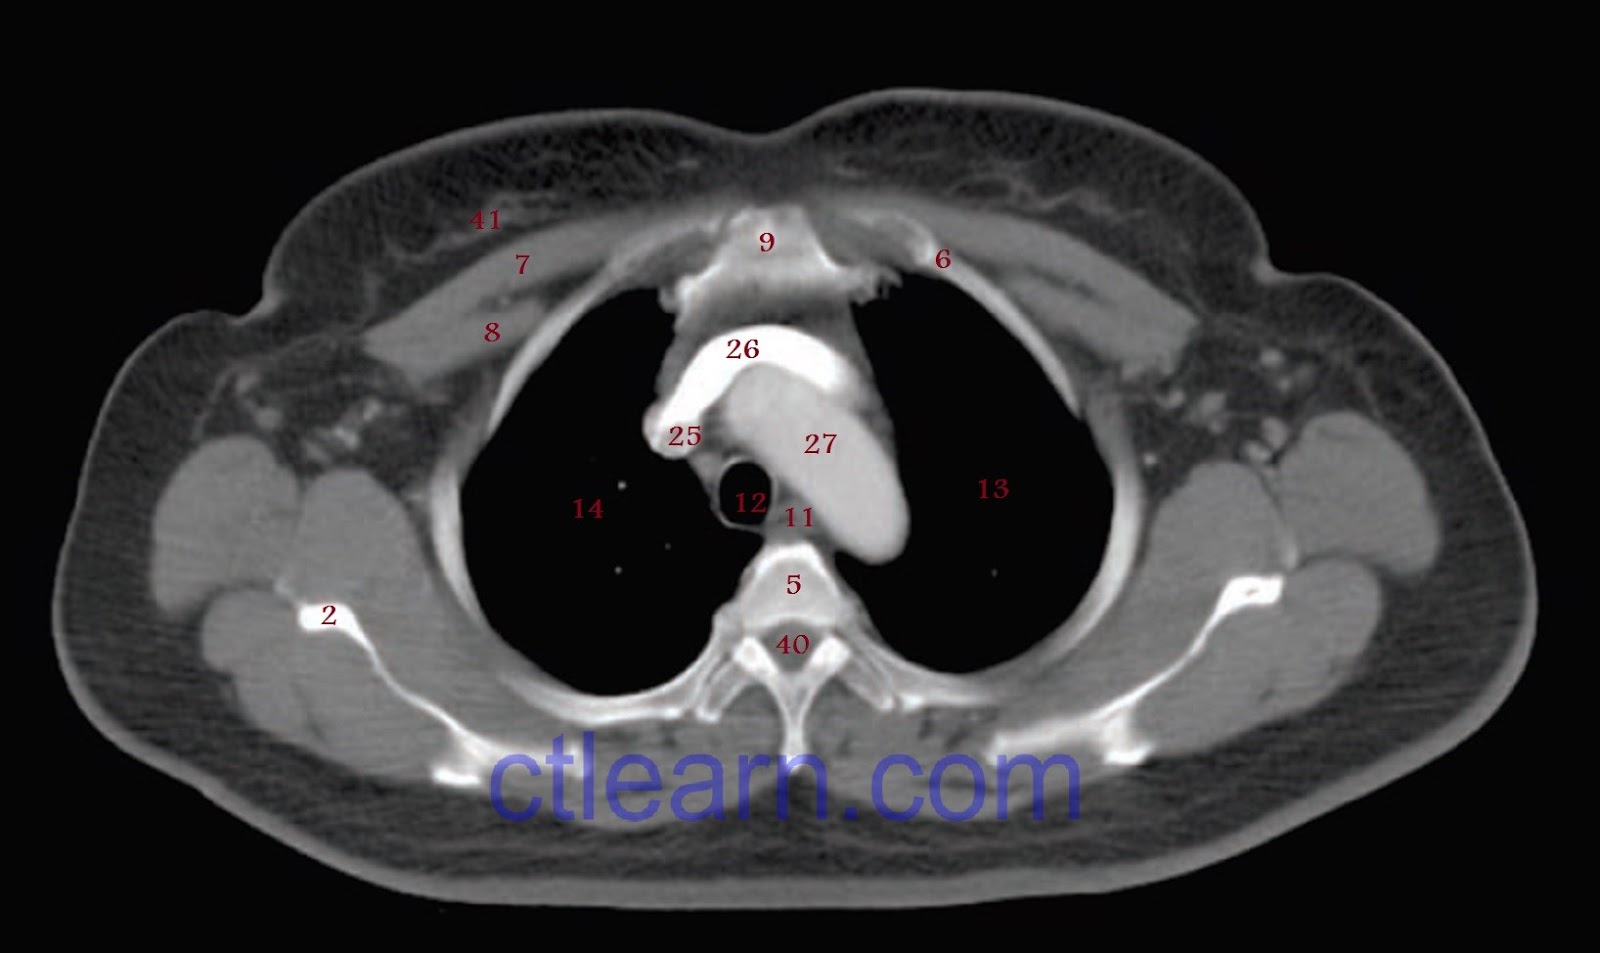

From www.ctlearn.com

Anatomy CT Axial Chest What Organs Show Up On A Chest Ct Scan This is especially true for. What is a chest ct scan? A ct scan of the chest may be done to check the chest and its organs for: Learn how to interpret ct scan results and understand what the findings mean. This article provides a comprehensive guide on. This imaging test can help your doctor diagnose a number of different. What Organs Show Up On A Chest Ct Scan.